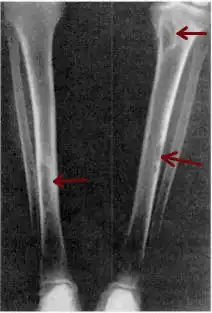

Osteitis fibrosa cystica of the tibia. Arrows point to the brown tumors which are typically present in bones of people with OFC. | |